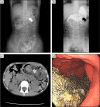

Management of foreign bodies ingestion in children